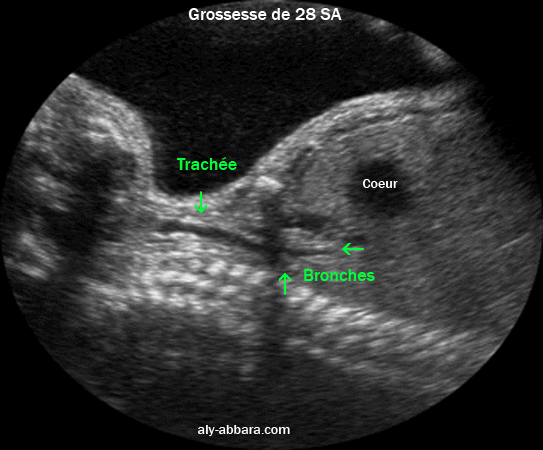

Coupe échographique sagittale médiane du cou et du thorax mettant en évidence la trachée et les deux bronches principales

fœtus âgé de 28 SA.